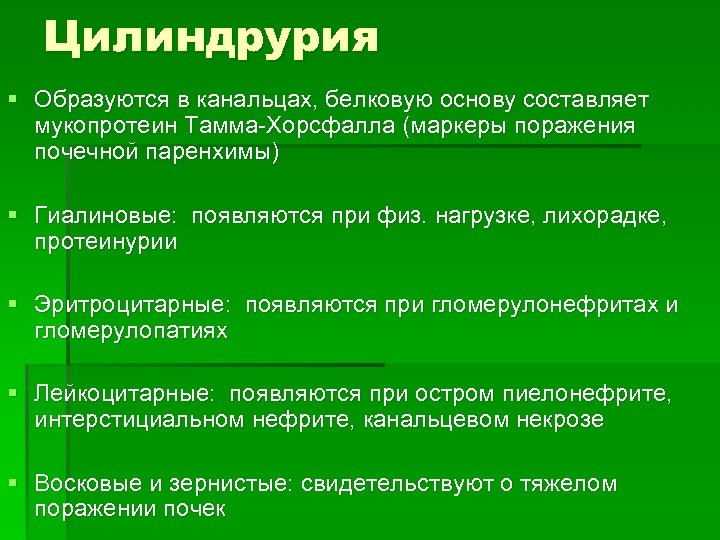

Цилиндрурия § Образуются в канальцах, белковую основу составляет мукопротеин Тамма-Хорсфалла (маркеры поражения почечной паренхимы) § Гиалиновые: появляются при физ. нагрузке, лихорадке, протеинурии § Эритроцитарные: появляются при гломерулонефритах и гломерулопатиях § Лейкоцитарные: появляются при остром пиелонефрите, интерстициальном нефрите, канальцевом некрозе § Восковые и зернистые: свидетельствуют о тяжелом поражении почек